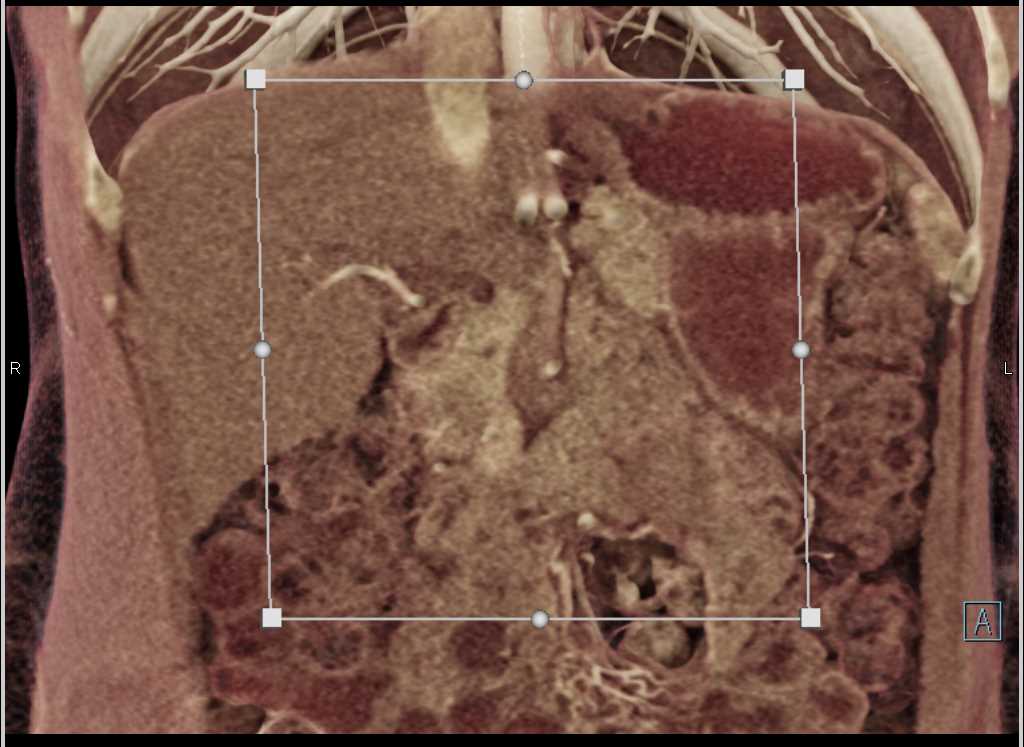

Intraductal Papillary Mucinous Neoplasm (IPMN) with High Grade Dysplasia